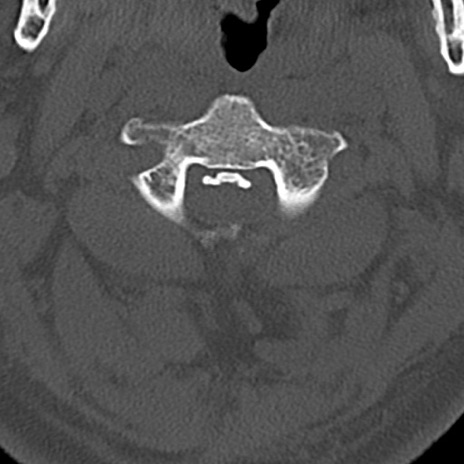

頚椎CT

横断像